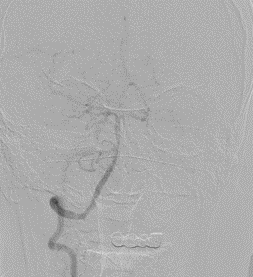

脑血管造影提示右侧颈内动脉颅内段多发动脉瘤(反主动脉弓)

脑血管造影提示右侧颈内动脉颅内段多发动脉瘤

4mm×30mm Streamline

术后4月余随访:多发动脉瘤均未见显影,远端残余轻度狭窄

术前术后对比